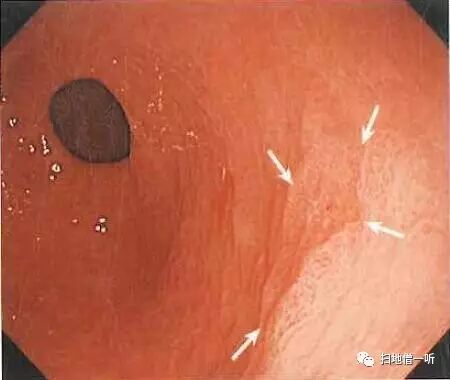

A:胃癌在图3及图6。HP未感染胃癌。

胃粘膜RAC阳性表现,提示HP未感染粘膜。胃体下部小弯侧可见小片状褪色粘膜。图3和图6是两个角度观察同一处病变。

靛胭脂喷洒然后后边界不清,表面无凸凹变化,为IIb型病变。无萎缩的胃底腺区域发现退色调病变,应怀疑印戒细胞癌。